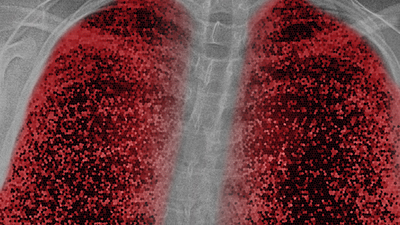

Yeni tip koronavirüs (Covid-19) ile enfekte olan hastaların 3 ay sonra yeni bir tarama yöntemiyle incelenen akciğerlerinde hasar tespit edildi. Oxford Üniversitesinden bilim insanları, yaşları 19 ila 69 olan 10 hastanın akciğerlerini ksenon gazı kullanarak manyetik rezonans (MR) ile taradı.

AA'nın BBC kaynaklı haberine göre, tarama sırasında ksenon gazını içine çeken hastalardan nefes darlığı çektiğini söyleyen 8'inde, akciğer hasarının işaretleri görüldü.

Hastaların Covid-19 enfeksiyonundan 3 ay sonra "nefes darlığının" yanı sıra "yorgunluktan" şikayetçi olduğu ancak enfeksiyon sırasında hiçbirinin yoğun bakıma alınmadığı ya da ventilasyona ihtiyaç duymadığı belirtildi.

HASAR GELENEKSEL TARAMA YÖNTEMLERİYLE TESPİT EDİLEMİYOR

Uzmanlar, hastalardaki akciğer hasarının, geleneksel tarama yöntemleriyle tespit edilemediğine de işaret etti.